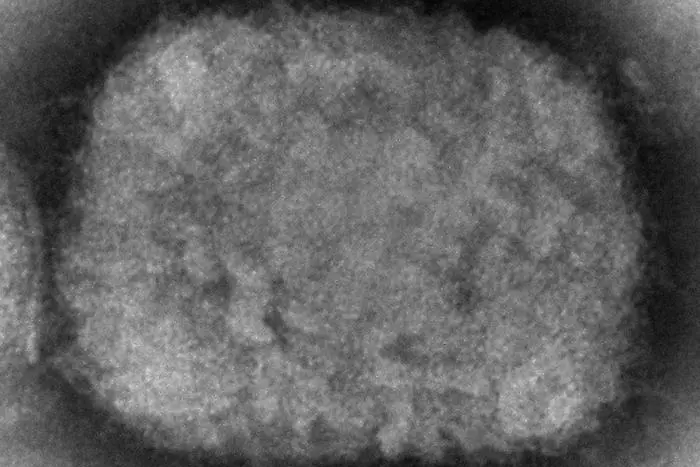

Първият случай на маймунска шарка в Европа бе регистриран във Великобритания. Последваха случаи в Португалия и Испания.

Де Кеерсмаакер припомни заключенията на Центъра, според които вирусът има умерена предаваемост сред хората, като има голяма вероятност той да се предаде чрез сексуален контакт, а възможността заразата да се пренесе между хора, които не са в близък контакт, е доста ниска.